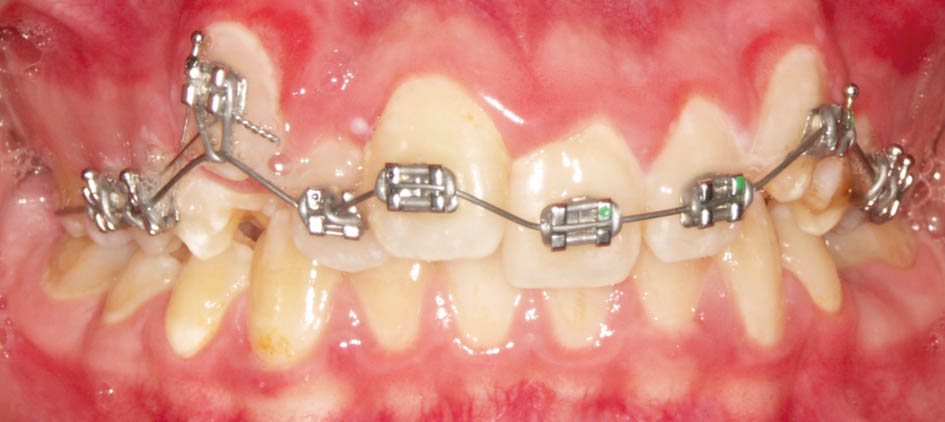

بعد از پروترودشدن قدامیها حالا میتوانید یک پلاک آندرسن (شکل 76-5 و 77-5) بسازید. میتوانید برای پلاک آرک لبیال نگذارید. در این مواقع مصرف پلاک تداخلی با داشتن براکتهای قدامی بالا ندارد و همزمان با مصرف این پلاک میتوانید سیم قدامیهای بالا را هم ضخیم کنید تا همزمان با رشد مندیبل، دندانهای بیمار هم مرتب شود.

درشکل78-5 و79-5 رابطه مولری یک کاسپ کامل کلاسII است و بعد از پروترود شدن قدامیهای بالا به کمک براکتها (شکل80-5) مندیبل هم حدود 3mm جلوتر قرار گرفته است.

در بیماران دیپبایت کلاسII جابجایی خلفی مندیبل خوب است چون با پروترود شدن قدامیها (تبدیل بیمار Div2 به Div1) مشکل کلاسII بیمار کمتر میشود و درمان فانکشنال زودتر تمام میشود. بعد از Div1 شدن پلاک فانکشنال بدهید و در یک دوره کمتر از 9 ماه شاهد کلاسI شدن بیمار (شکل81-5) میشوید.

شکل 80-5: پروترودشدن قدامیهای بالا باعث حذف فشار دیستاله روی مندیبل گشته و مندیبل جلوتر قرار میگیرد.

شکل 81-5: کلاسI شدن بیمار شکل 78-5 با پلاک فانکشنال آندرسن